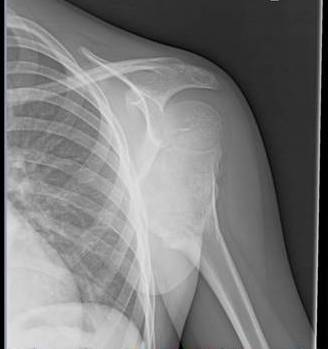

Exostosis-not always easy to identify!

Young Skeleton with pain after fall shows exophytic opacity outwards from the metaphyseal location of humerus with undisplaced fractures in the vicinity with almost 2 Humeral heads appearance suggesting exostosis with suspicion for secondary chondrosarcoma of cartilage cap. MRI is needed for further evaluation.

· Defined as developmental dysplasia of peripheral growth plate which forms cartilage cap projection of bone near metaphysis of long bones. Peripheral chondroblast grows outwards acting as ectopic growth plate , stopping at maturity

· X ray hallmark is blending of tumor in to the underlying metaphysis along with calcification of cap elements

· Only 1% solitary ones can turn secondary chondrosarcoma at the cap , with 10% in multiple variety

· Cartilage cap measuring >1cm in adults and 2-3 cms in children on MRI along with sudden increase in bone scan uptake in adults is of concern